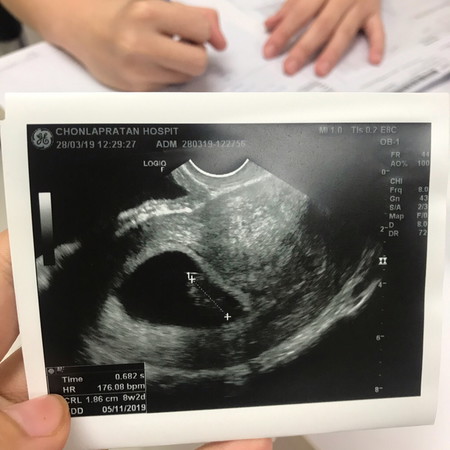

แบบนี้ปกติมั้ยค่ะ แม่ๆช่วยดูหน่อย

ขนาดเล็กไปมั้ยค่ะ

ก็ตามเกณฑ์นะคะสำหรับ8w

กี่วิคค่ะ